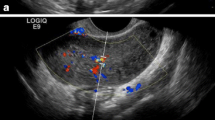

A 16-year-old patient was admitted in our emergency department with persistent abdominal pain in her right lower abdominal quadrant. The patient claimed that the pain was colic like, persistent and gradually advancing the last 2 months. Her medical history was free, her menarche was in the age of 13 years and her menstrual cycle had a periodicity of 28 days. The clinical examination revealed a palpable abdominal mass extending from the fossa iliaca to the liver. The patient was hemodynamic stable. After two doses of intravenous paracetamol the pain was alleviated. We performed a radiologic and laboratory control; our imaging control included an Ultrasound of the lower abdomen and a Ct Scan of the upper and lower abdomen. An intravaginal ultrasound control could not be performed because the patient was still virgin. The CT scan revealed a cystic lesion 23x15cm located in the right oblique abdominal area, from the liver to the minor pelvis, which is causing pressure to the right kidney and the bladder and a small fluid collection in the Douglas region. (Fig. 1) This finding combined with the laboratory values, which showed an elevated CA 125 marker of 57,9 and a normal function of the hepatobilliary and the urinary system, led us to make a decision to perform a laparotomy. We performed a subumbilical incision of the abdomen. The ovary was identified, it was very swollen and there was fluid in the rightovarian pedicle. This specimen was taken for cytologic examination, which was negative for malignancy. An incision of the ovarian mass followed in order to make it possible to remove the ovary from the abdomen. The structure was bulky without any fluid and the excision was very difficult. Intraoperatively, after performing a light traction of the ovary a triple partial torsion of the ovarian pedicle was seen, nevertheless, there were no signs of ischemia or necrosis of the ovary. After careful preparation of the ovary and the pedicle we performed the excision and the specimen (excised ovary) was sent as a frozen section material for histopathologic examination (Fig. 2). The result was negative for malignancy and was compatible with normal ovarian tissue. The left ovary had a normal anatomy without any evidence of pathology or dysfunction. Macroscopically, the excided ovary was a kidney-like, very oedematous structure 23x14x5 cm. There was no sign of necrosis or hemorrhage, but there were many cystic lesions on the upper surface of the ovary, with a maximum diameter of 1.5 cm and a serous content (Fig. 3). Afterwards we performed an appendectomy. The patient recovered very fast postoperatively, without any pain and symptoms. The pathologic examination revealed a stroma oedema with presence of many fibroblast and collagen fibre, cystic ovarian folicules with lutenization in the periphery of the ovary without any stromal changes (Fig. 4). In the appendix many parasitic worms were present of the type of Enterobius Vermicularis.